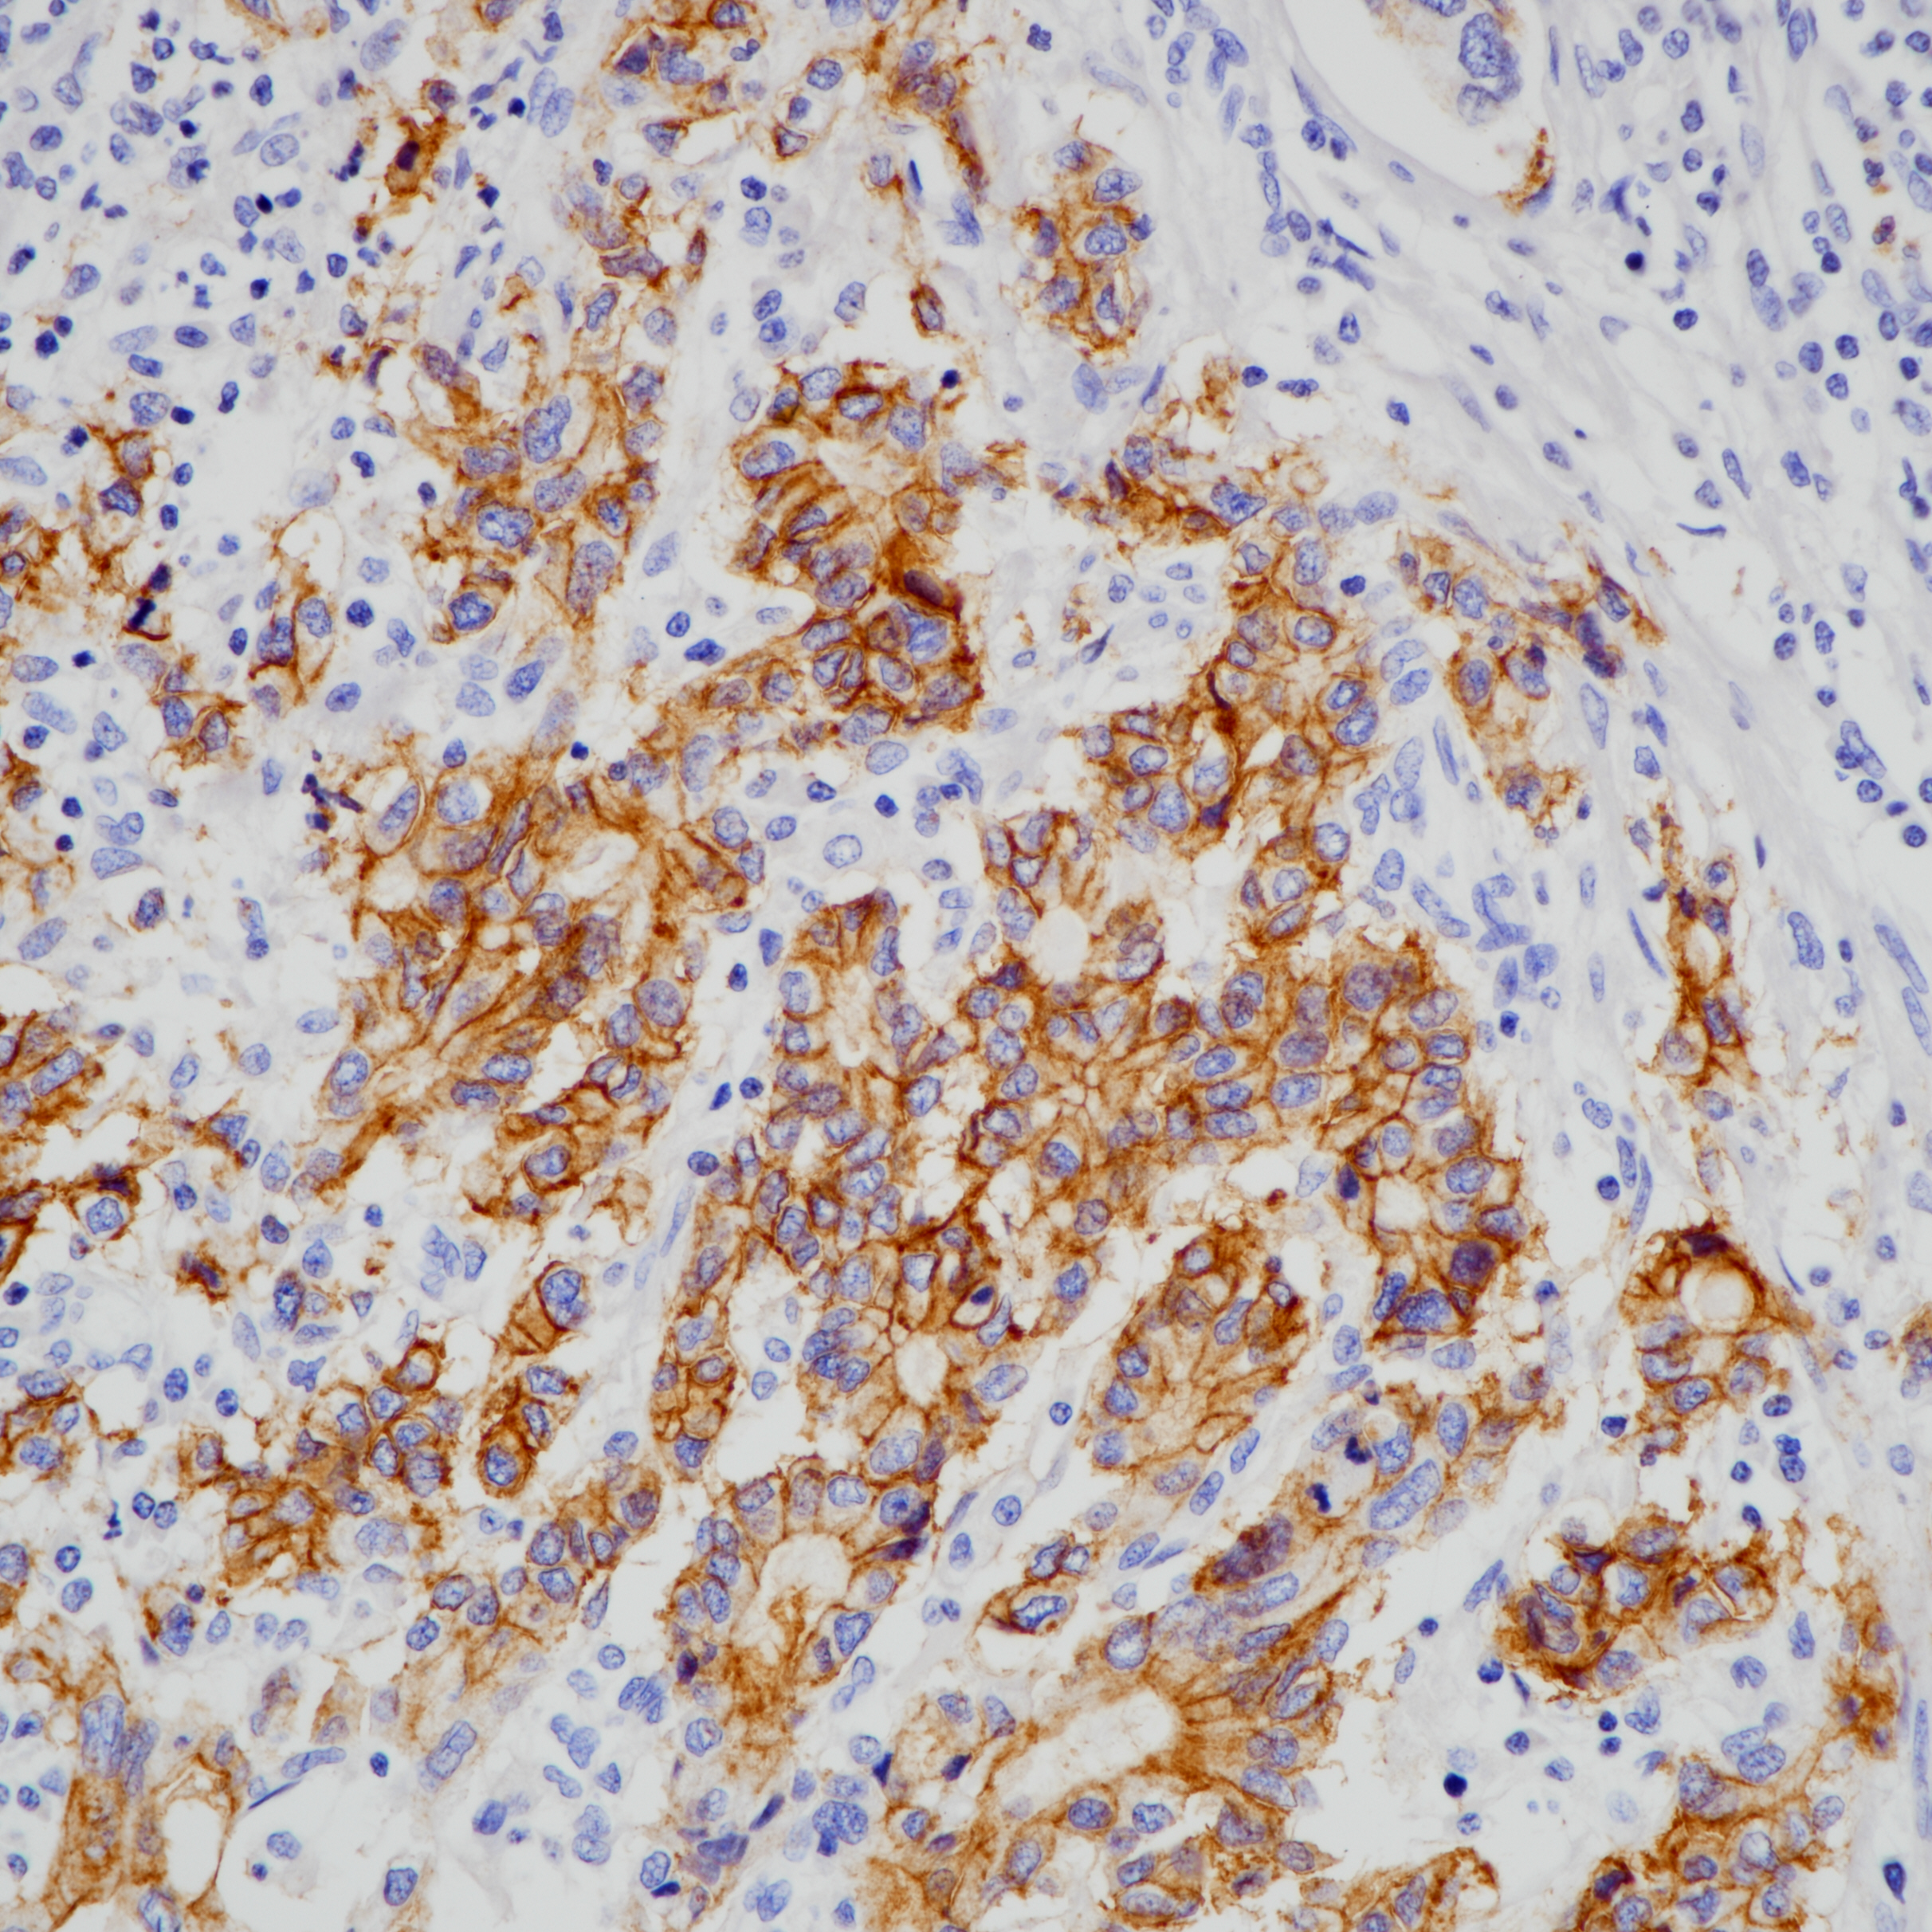

1. Clinical Implications of Claudin18.2 Expression in Patients With Gastric Cancer. [J] . Baek Jin Ho,Park Dong Jin,Kim Gyu Yeol,Cheon Jaekyung,Kang Byung Woog,Cha Hee Jeong,Kim Jong Gwang. Anticancer research . 2019 (12)

2. Expression of the potential therapeutic target claudin-18.2 is frequently decreased in gastric cancer: results from a large Caucasian cohort study. [J] . Dottermusch Matthias,Krüger Sandra,Behrens

Hans-Michael,Halske Christine,R?cken Christoph. Virchows Archiv : an international journal of pathology . 2019 (5).

3. Comparison of Claudin 18.2 expression in primary tumors and lymph node metastases in Japanese patients with gastric adenocarcinoma. [J] . Rohde Christoph,Yamaguchi Rin,Mukhina Svetlana,Sahin Ugur,Itoh Kyogo,Türeci ?zlem. Japanese journal of clinical oncology . 2019 (9).